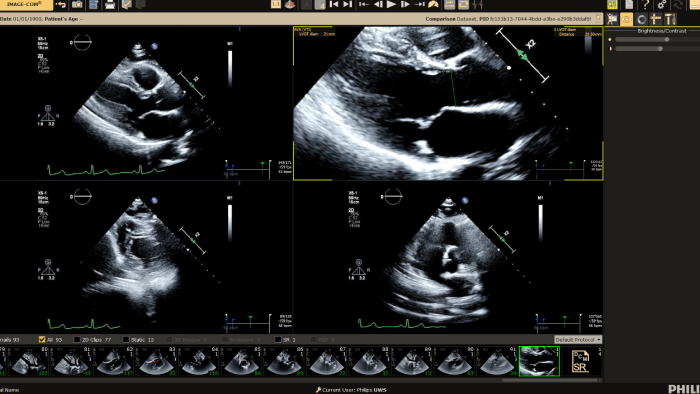

Ultrasound Workspace

Allow for greater efficiency in viewing, analysis and reporting by giving care teams the flexibility to adopt different workflows based on their current and future needs.

Cardiovascular Workspace

Provide a single point of access to patient’s cardiovascular diagnostic information and multi-modality images at excellent diagnostic quality, including prior exams, as well as findings, measurements, and reports.